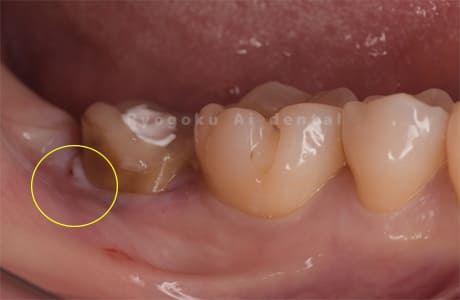

Case05

-

- 原因

- 慢性根尖性歯周炎

- 治療内容

- マイクロエンド

- 治療費用

- 121,000円(被せ物は含まない)

他院ではお薬の交換と抗生剤の処方で経過を診ていた患者さんです。歯茎の腫れが治らないとのことで、根管治療を開始し、2回目のご来院で腫れが引いたケースです。現在は被せ物も入り、良好に経過しております。

<リスク・副作用>

術後は痛み、腫れ、痺れなどの副作用が生じる場合があります。症状が再発する可能性があります。